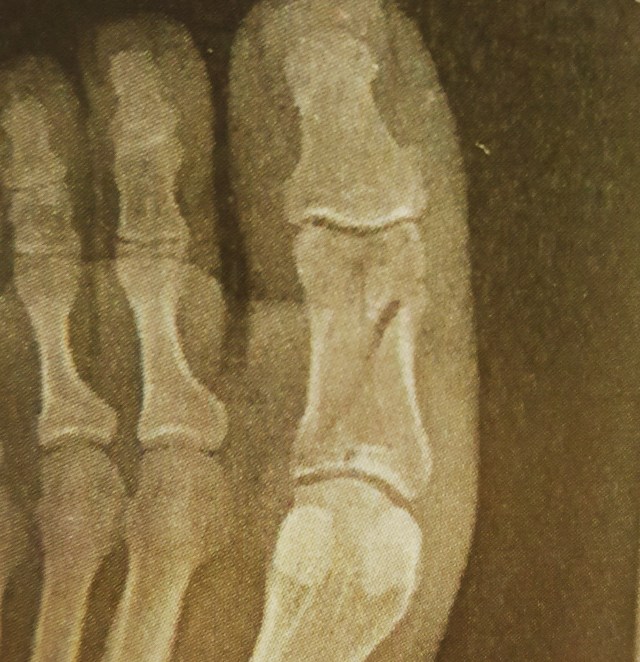

I didn’t let my toe slow me down much in classes either. I missed the one day for my orthopedic appointment where I was told no surgery would be needed as the bone is aligned nicely, but if it were the increased mobility of my fingers it would be a different story. I spent all but the last two of my spin classes on a mat doing push-ups, abs, and headstands — and the crutches with the boot helped improve my upper body strength and allow me to hold the pose for one minute.

I switched from a knee-high boot to a below the ankle shoe Nov. 27 and was so happy to move my joints again. This has helped me improve my stationary bike time from 5 to 9.5 miles in 30 minutes. I’m not allowed to run or jump yet, but have another appointment on January 4th for more x-rays to assess my progress. It took about 5.5 weeks before I braved a standing shower and it felt so liberating, but I still prop my foot up with my glass shower doors during my shortened showers.

It feels good to be able to wiggle my toes again and I feel the need to pop my second toe, but the toes are still swollen and I have lots of dead skin that I still soak in the bath. I should be wearing a boot of my own soon and hope that helps with the walking, and gaining the inch and a half back that I lost in my calf. People have noticed my foot goes in a bit, but without an arch or being able to toe off I do walk funny, but I don’t want it to effect my back, hip, or knee. I went to the chiropractor Dec. 20th and he said I’m doing great, but to keep an eye on my foot. Aye, aye, Doc.